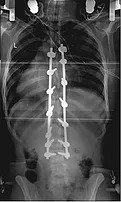

In TLIF, the surgeon approaches the spine from the back through a posterior incision. The disc at the affected level is removed through a channel created in the foramen (neural opening), and a cage is placed in the disc space. Pedicle screws and rods are then placed to provide immediate stability while the bone fuses.